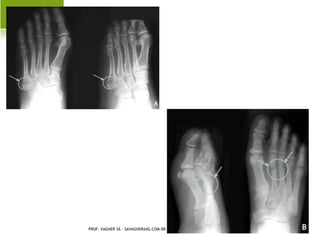

H ÁLUX VALGO A DQUIRIDO

H ÁLUX VALGOA DQUIRIDO PROF. VAGNER SÁ - SAVAGNER@IG.COM.BR